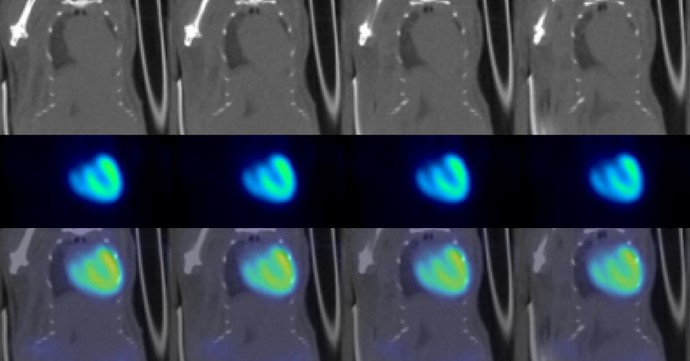

Cardiovascular Imaging